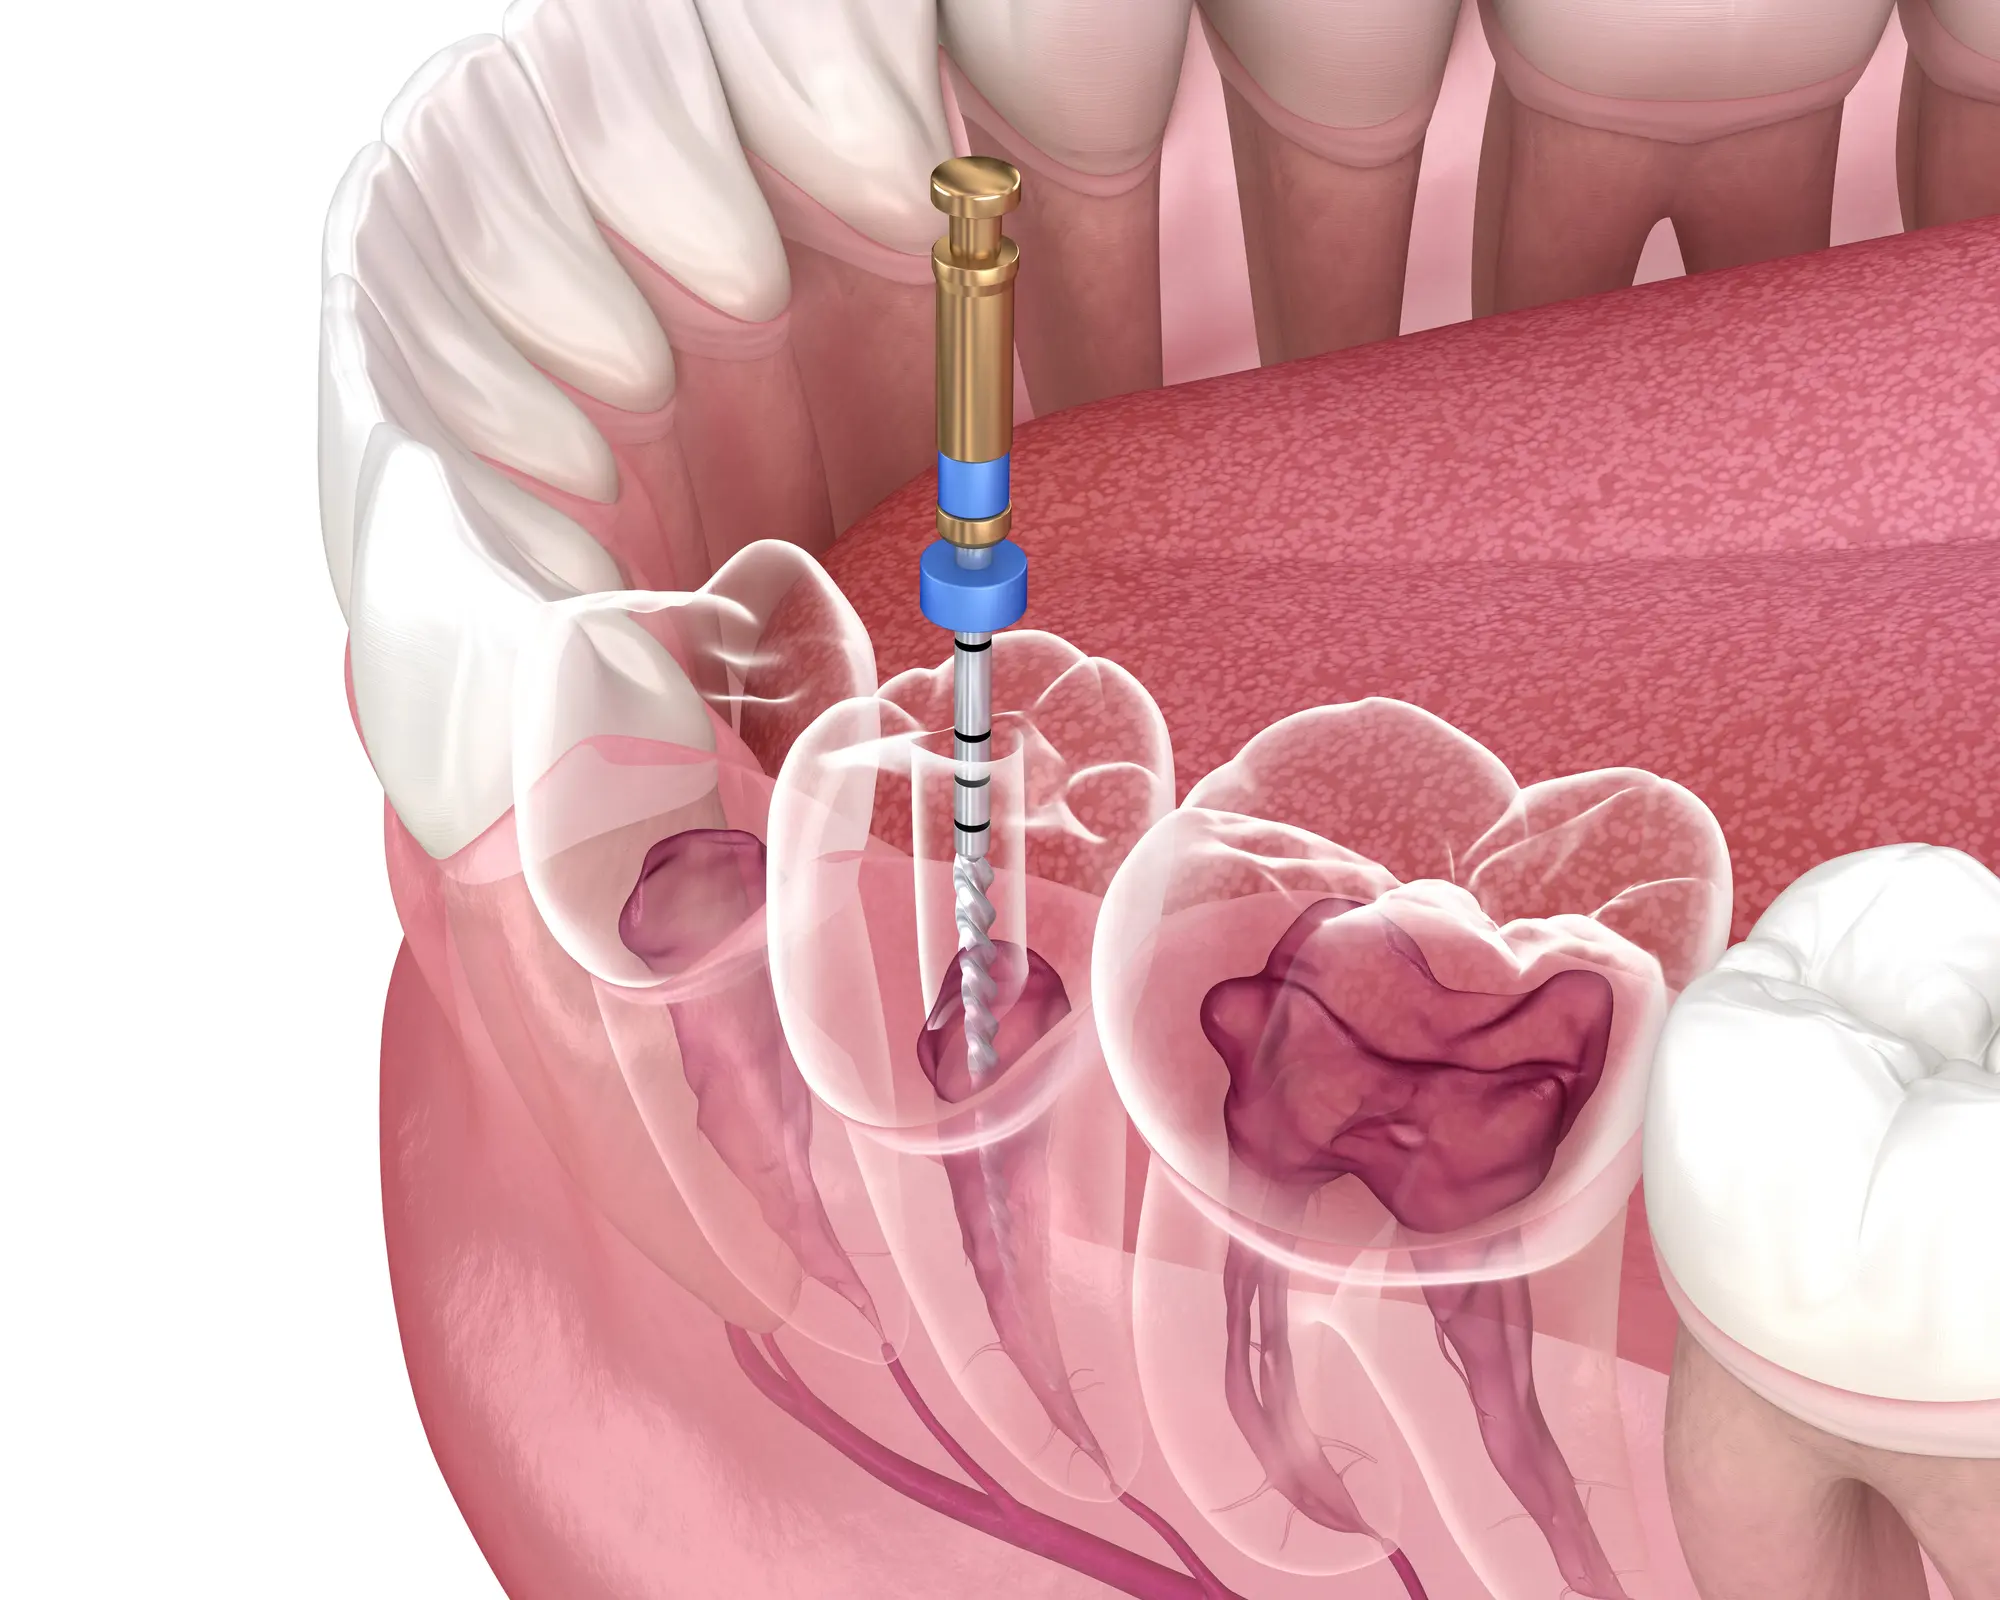

A non-surgical root canal is a minimally invasive procedure designed to remove infected or damaged pulp, the soft center containing blood vessels that help support your tooth.

What Happens During a Non-Surgical Root Canal?

The procedure begins with local anesthesia to keep you comfortable. In some cases, nitrous oxide may also be offered for extra relaxation. Once numb, the dentist carefully removes the infected pulp, cleans the canal system, and seals it to prevent reinfection.